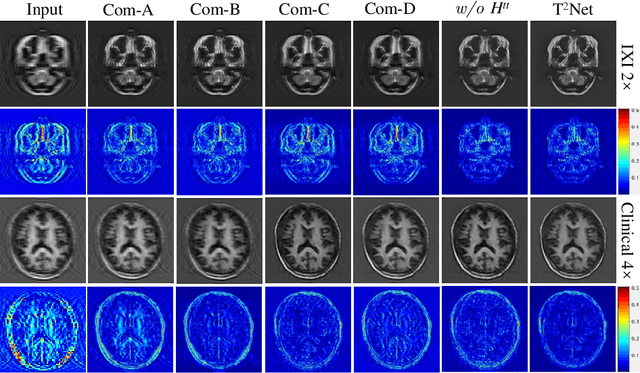

Abstract:The core problem of Magnetic Resonance Imaging (MRI) is the trade off between acceleration and image quality. Image reconstruction and super-resolution are two crucial techniques in Magnetic Resonance Imaging (MRI). Current methods are designed to perform these tasks separately, ignoring the correlations between them. In this work, we propose an end-to-end task transformer network (T$^2$Net) for joint MRI reconstruction and super-resolution, which allows representations and feature transmission to be shared between multiple task to achieve higher-quality, super-resolved and motion-artifacts-free images from highly undersampled and degenerated MRI data. Our framework combines both reconstruction and super-resolution, divided into two sub-branches, whose features are expressed as queries and keys. Specifically, we encourage joint feature learning between the two tasks, thereby transferring accurate task information. We first use two separate CNN branches to extract task-specific features. Then, a task transformer module is designed to embed and synthesize the relevance between the two tasks. Experimental results show that our multi-task model significantly outperforms advanced sequential methods, both quantitatively and qualitatively.